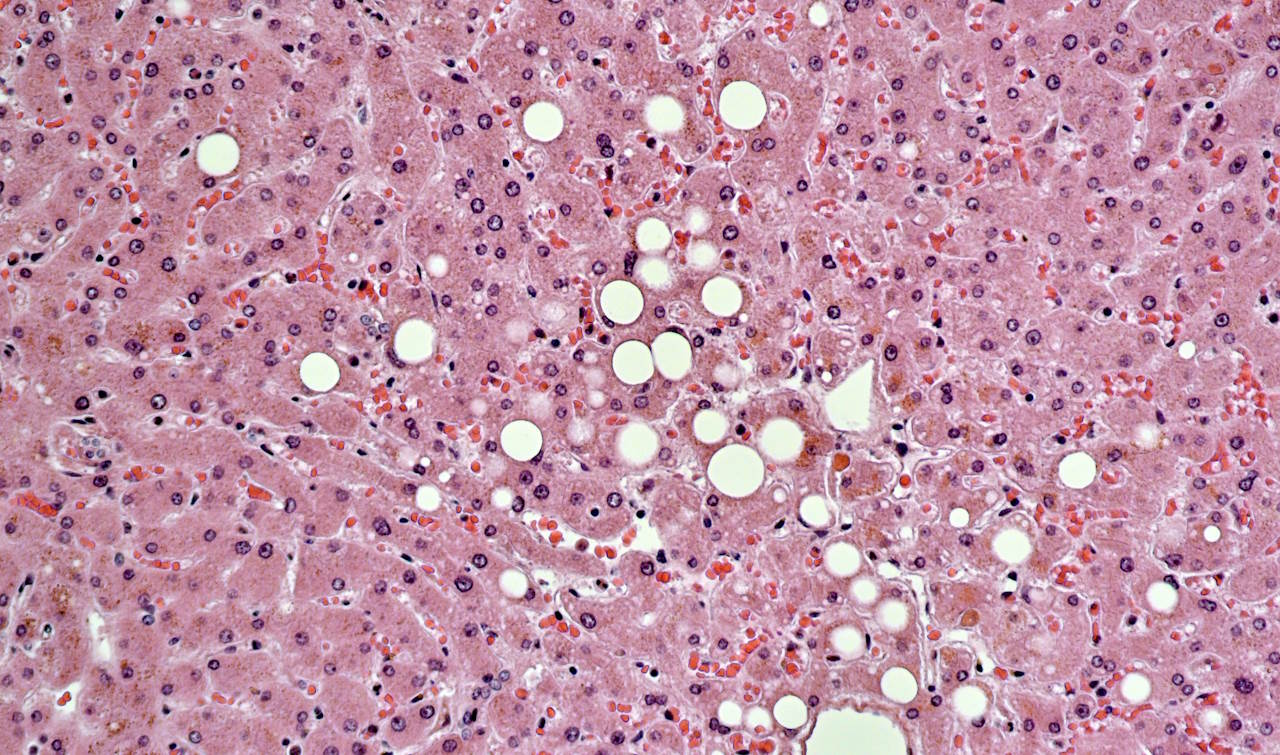

Швидке схуднення, зумовлене різким обмеженням споживання калорій, покращило здоров’я печінки у людей із ожирінням і неалкогольним стеатогепатозом — запальною хворобою печінки при заміщенні її тканин жировими клітинами та сполучною тканиною. На це вказує дослідження британських науковців у журналі Obesity.

Неалкогольний стеатогепатоз зазвичай розвивається на фоні надмірної ваги тіла, і зі збільшенням у світі частки людей з ожирінням зростає й кількість людей із захворюванням печінки. Оскільки воно пов’язане із зайвою вагою, при його лікуванні ключова роль належить схудненню. Згідно з більшістю досліджень, вагомого покращення стану печінки можна досягти при скиданні 15-20 відсотків ваги. Зробити це у відносно короткі терміни можна завдяки дуже низькокалорійній дієті.

За 24 тижні на дієті учасники втратили 15 відсотків ваги. За цей час частка жиру у їхній печінці зменшилася у середньому на 13 відсотків, а в 10 добровольців показник складав у кінці менш ніж 5,6 відсотка, що вказує про усунення надмірного жиру в органі. Про краще здоров’я печінки після дієти свідчили й суттєво нижчі показники АЛТ та АСТ у крові, які є маркерами пошкодження печінки.